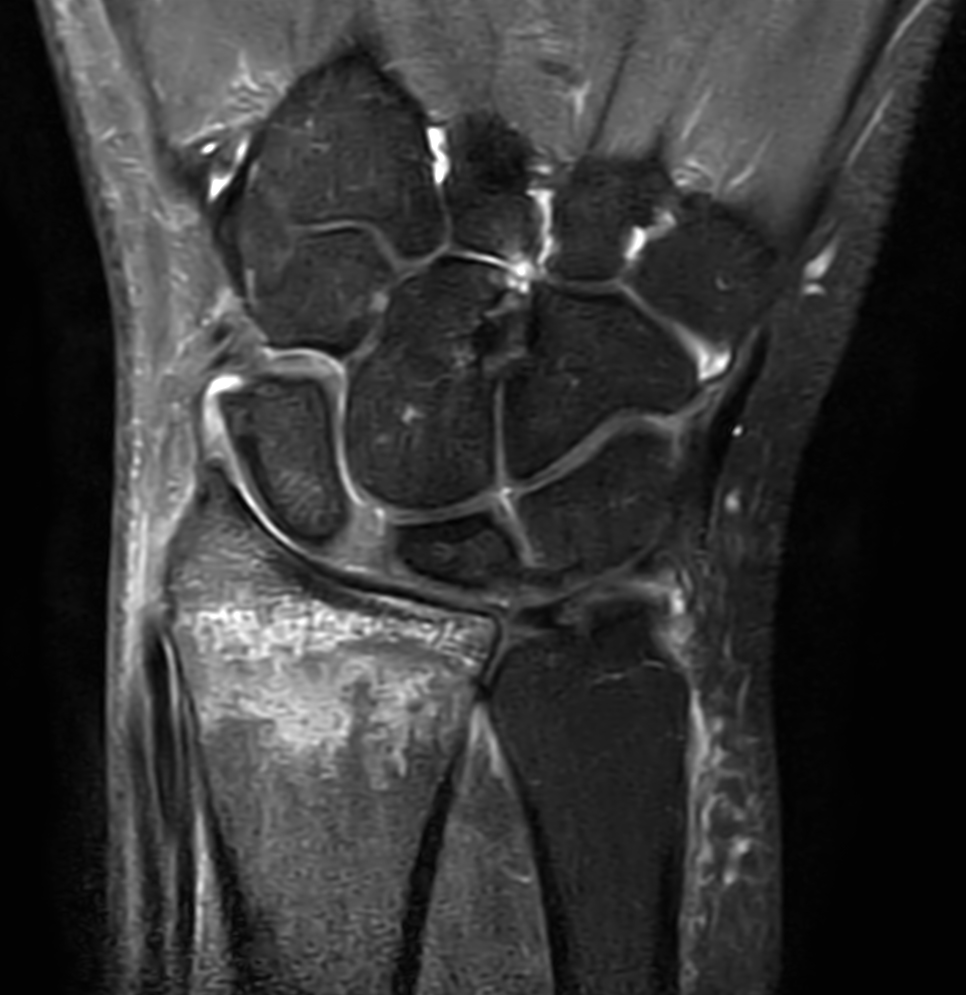

Patient with a wrist fracture. Compressed SENSE is used in all sequences, reducing the scan time while maintain equal image quality compared to scans without Compressed SENSE. 3D sequences have been added to this ExamCard with a comparable in-plane resolution but much thinner slices. Due to the shorter scan times that can be achieved thanks to Compressed SENSE, these 3D sequences could potentially replace the 2D sequences providing more confidence in making the diagnosis.

2D Coronal PDw SPAIR